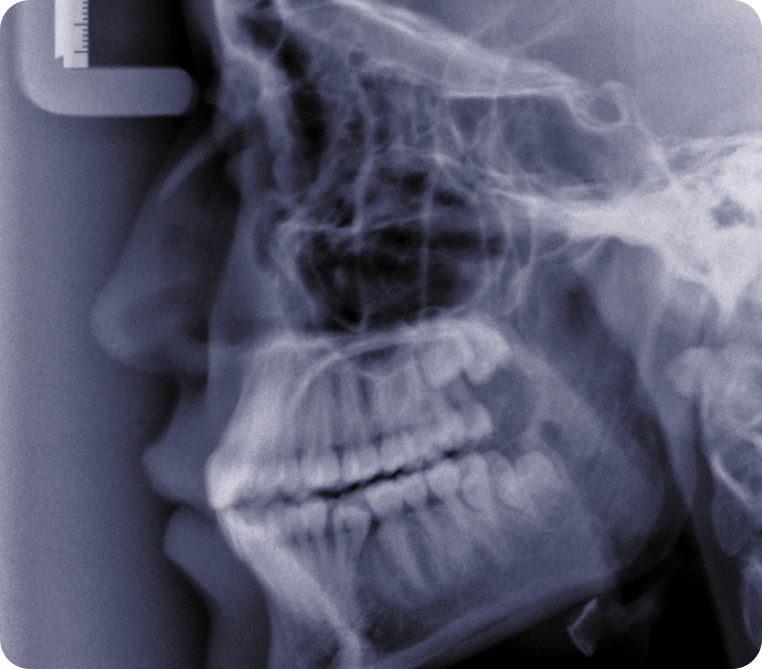

코는 얼굴에서 비교적 약한 부위이면서 돌출되어 있어 얼굴에 외상을 입을 경우 가장 흔히 골절되는 부위입니다. 코의 위쪽은 단단한 뼈로, 아래쪽은 부드러운 연골로 되어 있으며 외상을 입어 코의 위쪽을 이루는 뼈가 골절 되어 코 모양이 변하거나 주저앉는 것을 말합니다. 코뼈 골절의 진단은 신체진찰을 포함한 이학적 검사 및 Xray, CT를 통해 정확히 진단이 가능합니다.